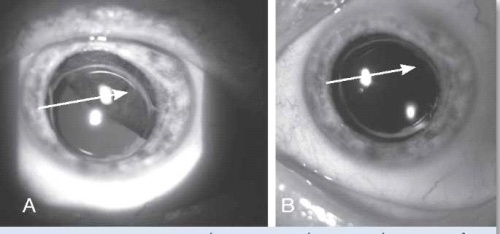

הקרנה סלקטיבית של העין באמצעות לוחית מתכת (פלאק) המונחת על פני לובן העין (Sclera) ומשחררת קרינה רדיואקטיבית לתוך חלל העין, ישירות על בסיס הגידול (ראו ציור 1). הטיפול נעשה בשני ניתוחים עוקבים. בניתוח הראשון הלוחית מקובעת ללובן העין, ובניתוח השני מוסרת ממקומה.

TTT) Transpupillary Thermotherapy)

בגידולים אחוריים מסוימים נהוג להוסיף חימום של הגידול, בדרך כלל באמצעות טיפול בלייזר Diode, כטיפול אדג׳ובנטי לברכיתרפיה. זהו לייזר המרכז קרן אור אינפרה אדום באורך גל 810 ננומטר ישירות על תאי הגידול, ומחמם את התאים לטמפרטורה של 60-45 מעלות. אפשר להשתמש בשיטה זו בחדר הניתוח או כטיפול במרפאה לאחר הרחבת אישונים והקרנה דרך האישון הרחב. הנזק התרמי בשילוב עם הנזק הקרינתי מסייעים להשגת שליטה טובה יותר על הגידול התוך עיני, מבלי להוסיף נזק סביבתי לרשתית התקינה סביב הגידול. שילוב של שתי שיטות הטיפול הוריד את אחוזי ההישנות ל-3% בלבד במעקב של חמש שנים על פי Shields וחברים[5] (ראו ציור 1).

שיטת טיפול זאת יכולה לשמש כשיטת טיפול יחידה בגידולים קטנים נבחרים (בעובי מתחת ל-3 מ"מ) שאינם ממוקמים במרכז הראייה או על פני עצב הראייה.